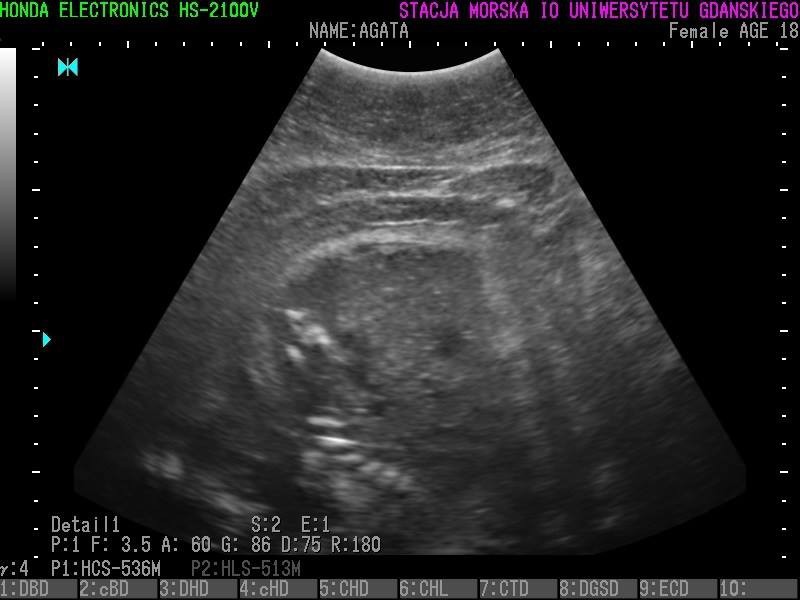

Wszystkie helskie foki - czyli Agata, Ewa, Unda Marina i Ania - są w ciąży. To wyniki badań ultrasonograficznych, które przeprowadzono w miniony piątek (23 grudnia).

• Z radością więc informujemy, że tego roku wszystkie nasze cztery samice spodziewają się potomstwa - czytamy na profilu Fokarium.

Szczenięta urodzą się najprawdopodobniej w marcu 2017 roku.